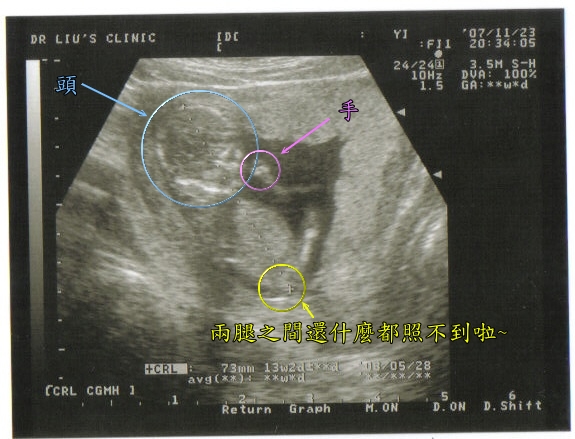

大家看的出來這是什麼嗎~~(其實在我沒懷孕之前~大家的超音波我實在是有看沒有懂啊~)~

所以為了方便大家了解~這團黑黑的到底是什麼~~我特別做了圖解~~

哎~虧這次小米同學腿還開大大的~可是什麼都不知道~~整個殘念~~

大家看的出來這是什麼嗎~~(其實在我沒懷孕之前~大家的超音波我實在是有看沒有懂啊~)~

所以為了方便大家了解~這團黑黑的到底是什麼~~我特別做了圖解~~

哎~虧這次小米同學腿還開大大的~可是什麼都不知道~~整個殘念~~